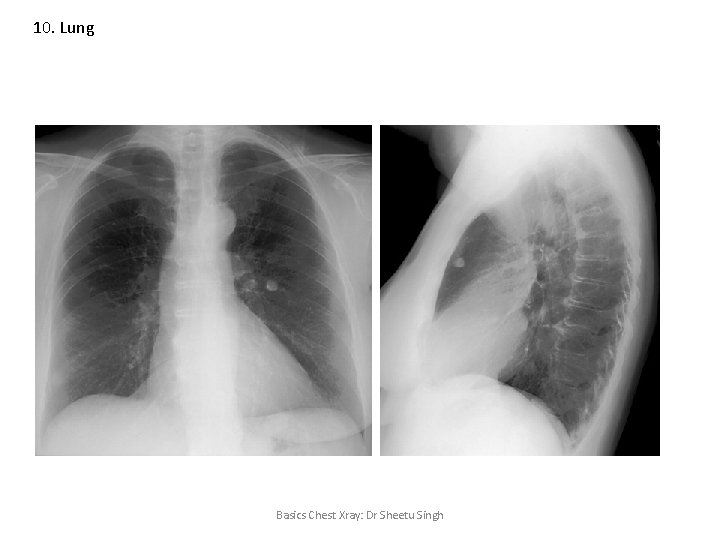

10. Lung Solitary pulmonary nodule • A solitary pulmonary nodule is defined as a discrete, well-marginated, rounded opacity less than or equal to 3 cm in diameter that is completely surrounded by lung parenchyma, does not touch the hilum or mediastinum, and is not associated with adenopathy, atelectasis or pleural effusion. • Lesions larger than 3 cm are considered masses and are treated as malignancies until proven otherwise. Basics Chest Xray: Dr Sheetu Singh

10. Lung Solitary pulmonary nodule Hamartoma: popcorn calcification Non cavitating nodules Diagnosis: CT chest CT guided FNAC/Biopsy Basics Chest Xray: Dr Sheetu Singh